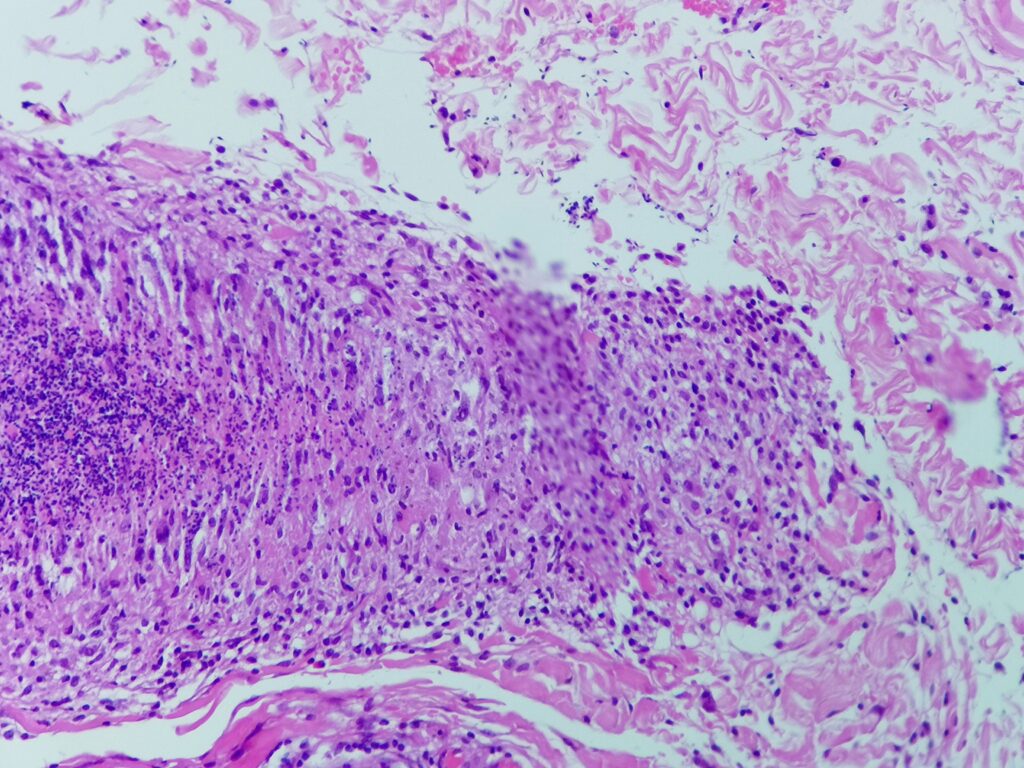

Obrazy mikroskopowe:

Cechy charakterystyczne:

- cienkościenna torbielowata struktura składająca się z tkanki łącznej (krzyżyk) wysłana jednowarstwowym nabłonkiem (czerwona strzałka) od kostkowego po walcowaty, z pojedynczymi komórkami rzęskowymi – torbiel nasienna patrz przypadek nr 105. SMP

- poza światłem zmiany obecne są plemniki (gwiazdka) z otaczającym odczynem z histiocytów (komórki o owalnym lub okrągłym jądrem komórkowym stosunkowo obfitej lekko kwasochłonnej cytoplazmie, niebieska strzałka), nieliczne limfocyty i komórki wielojądrowe (zielona strzałka) – ziarniniak

- brak komórek atypowych, martwicy centralnej, grzybów bądź innych mikroorganizmów

Ziarniniak nasienny (sperm granuloma)